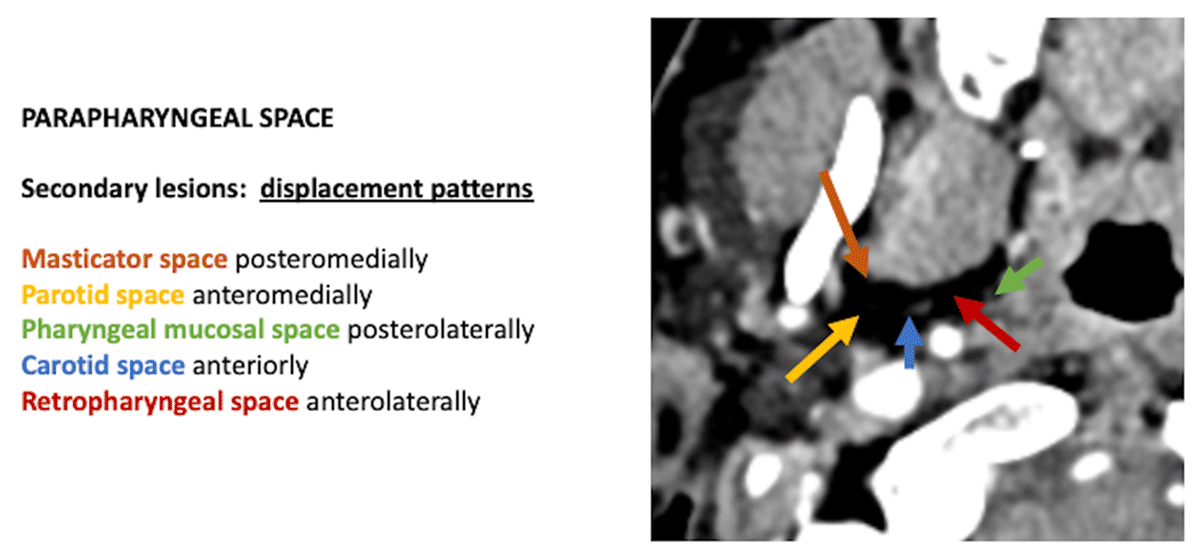

Figure 1

The secondary displacement patterns of the fat in the parapharyngeal place may help to localize pathology in the surrounding spaces and aid in the space-specific diagnosis of pathology in the suprahyoid neck.